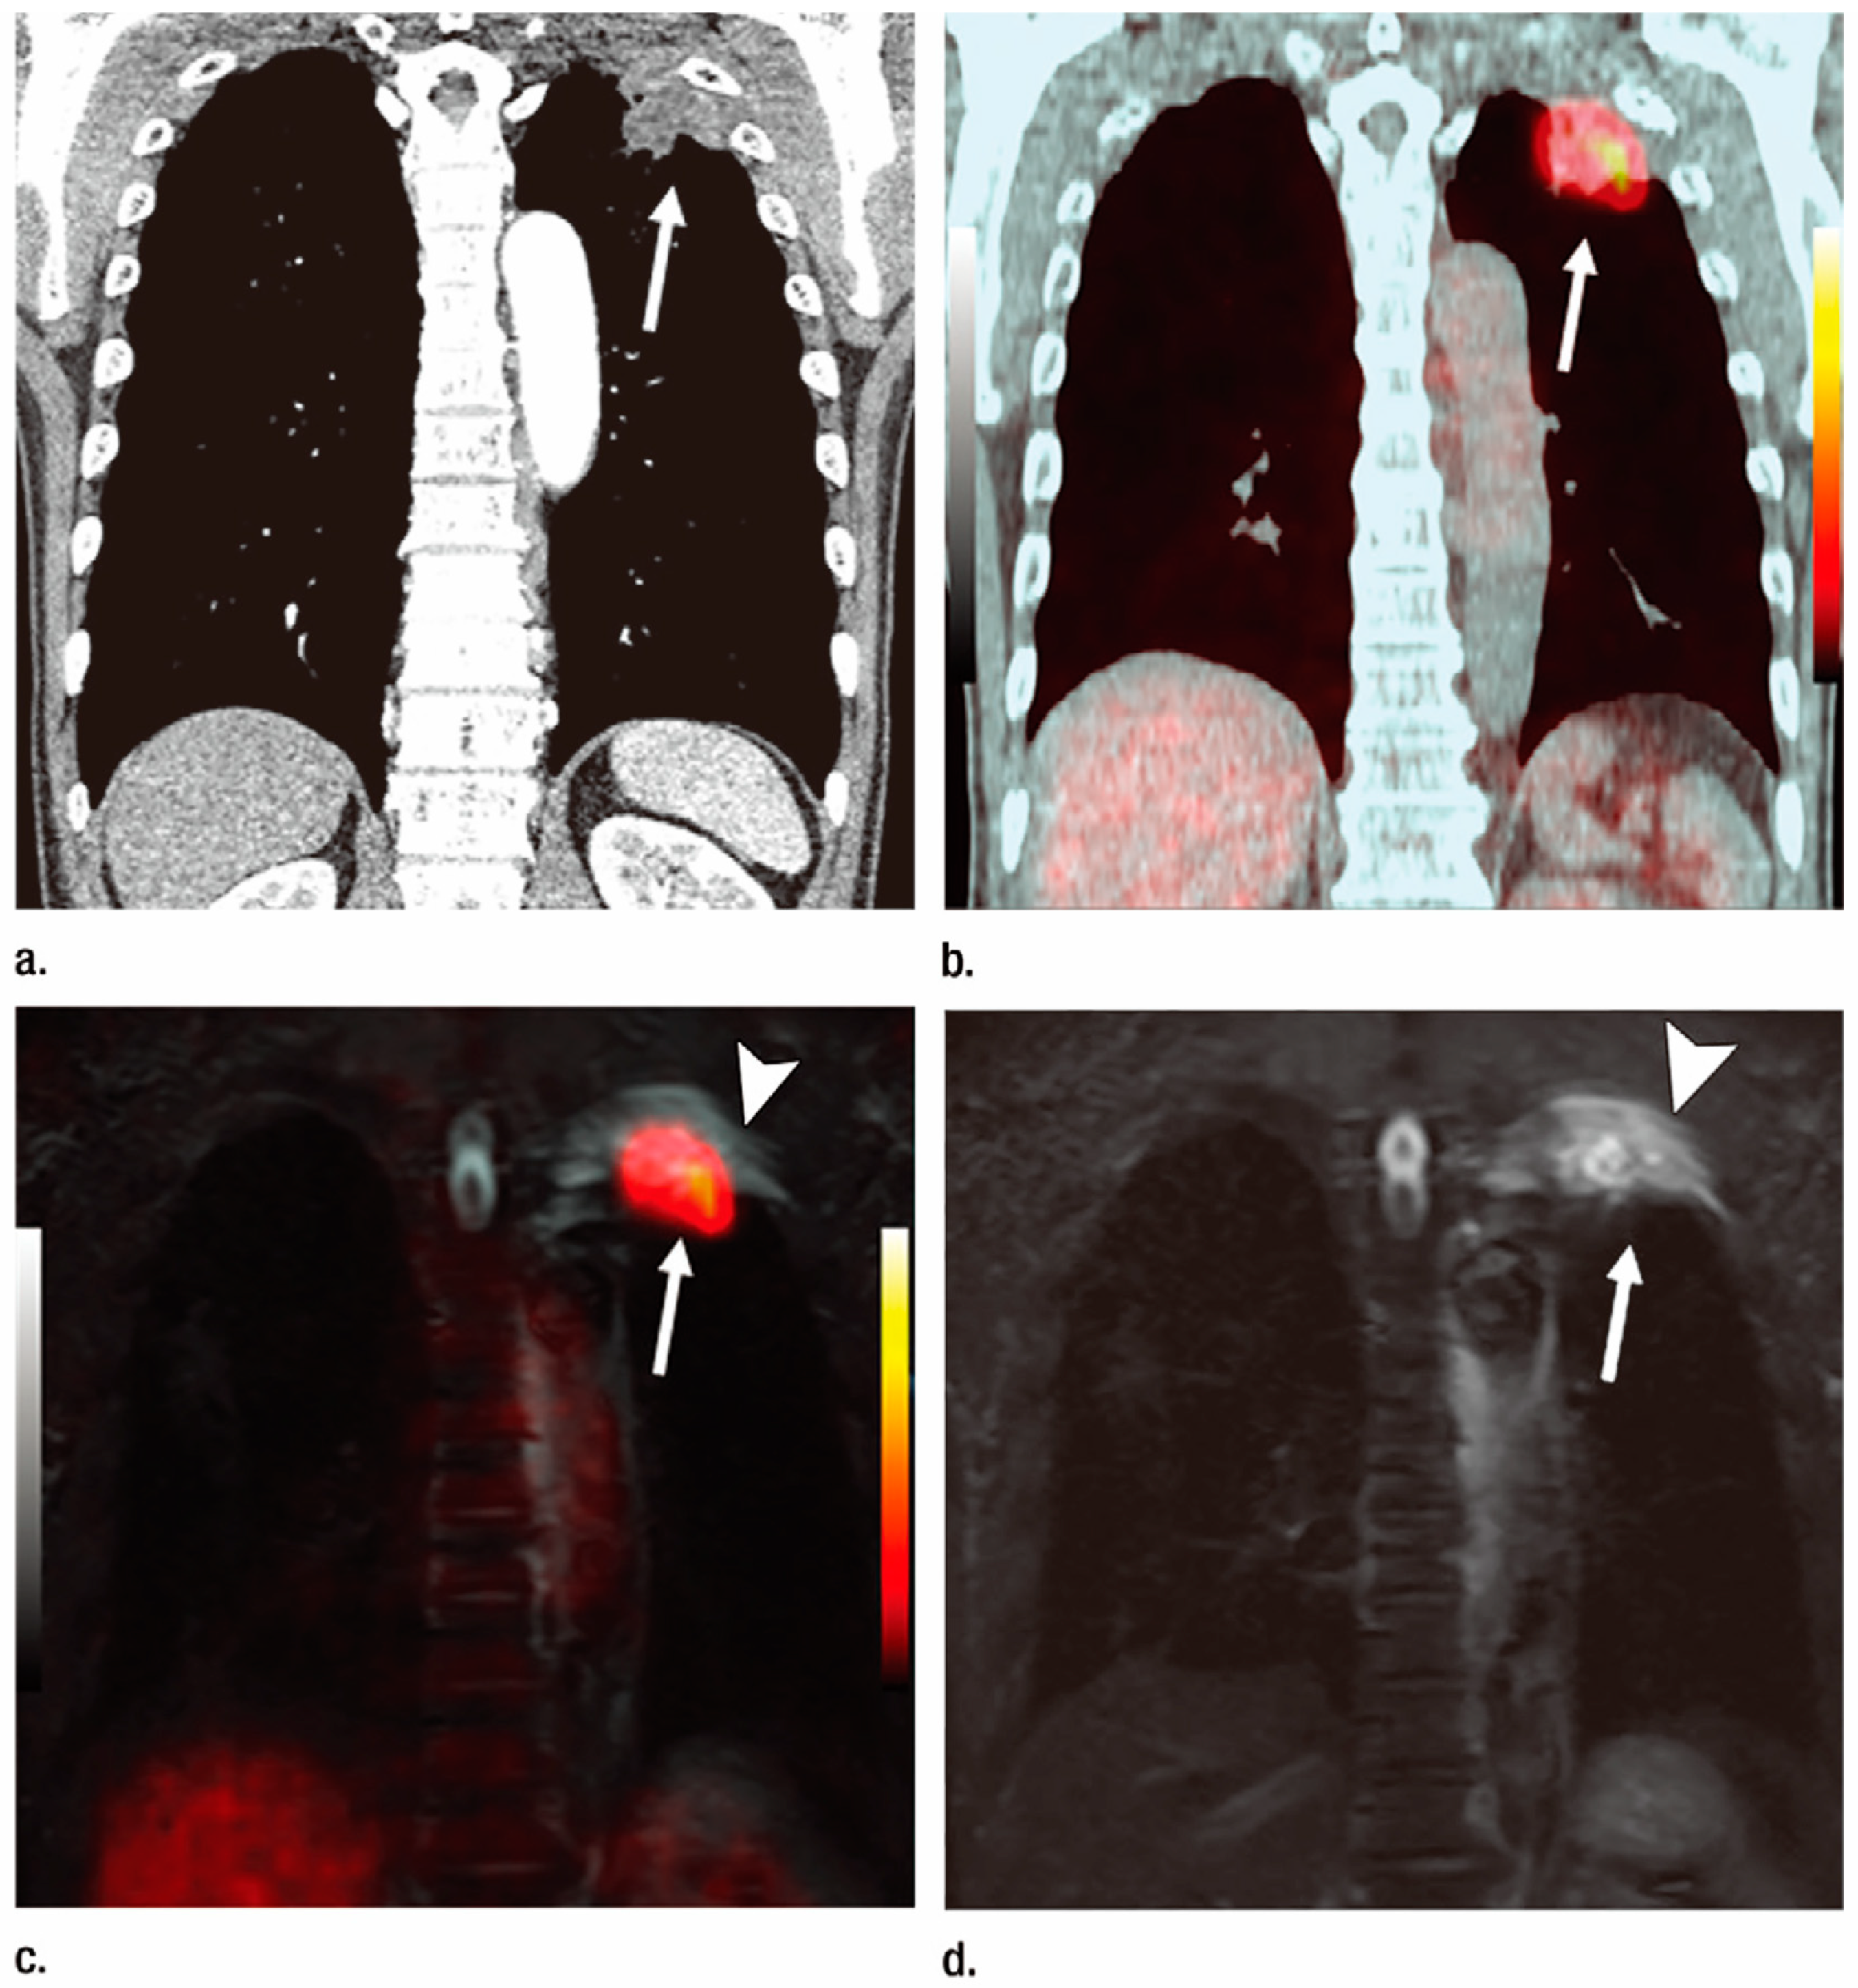

3.1. T-Factor Assessment